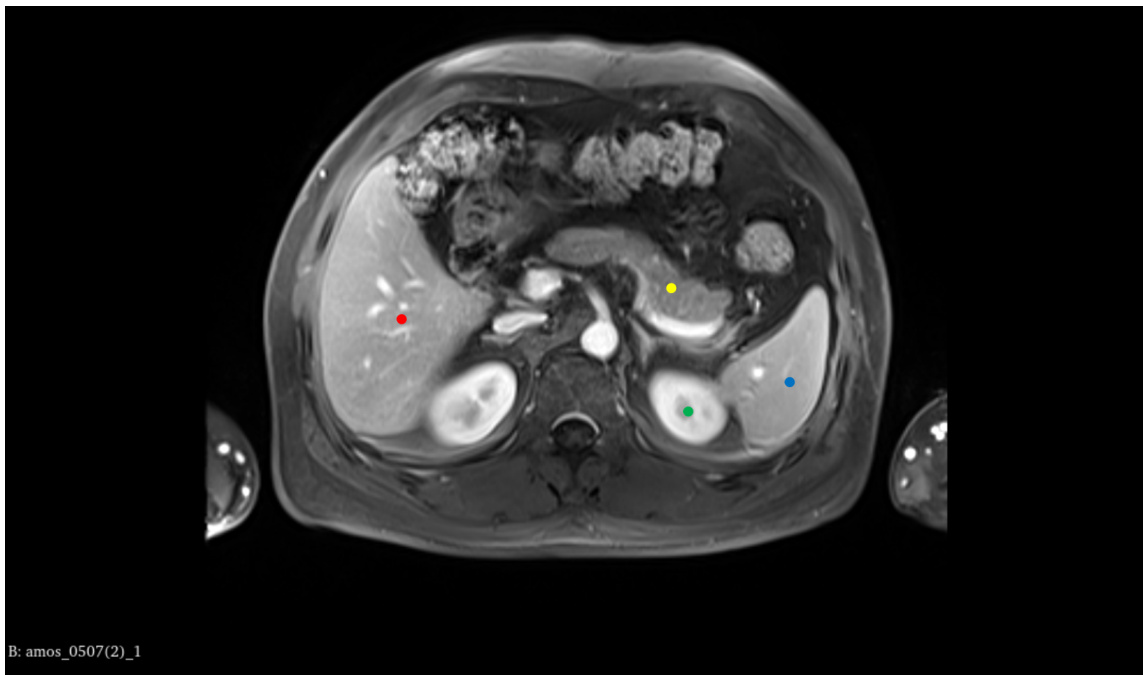

• Picture modal: MRI section • Tasks: Abdominal MRI section • Reference Answer: – Red Dot: Liver. – Yellow Dot: Pancrea. – Green Dot: Left kidney. – Blue Dot: Spleen.

- 图片模态:MRI切面

- 任务:腹部MRI切面

- 参考答案:

- 红点:肝脏。

- 黄点:胰腺。

- 绿点:左肾。

- 蓝点:脾脏。

CASE 3 Control Group

案例3 控制组

Prompt: This is an abdominal MRI scan. Please tell me what organs are marked by the four different colors.

提示:这是一张腹部 MRI 扫描图。请告诉我四种不同颜色分别标记了哪些器官。